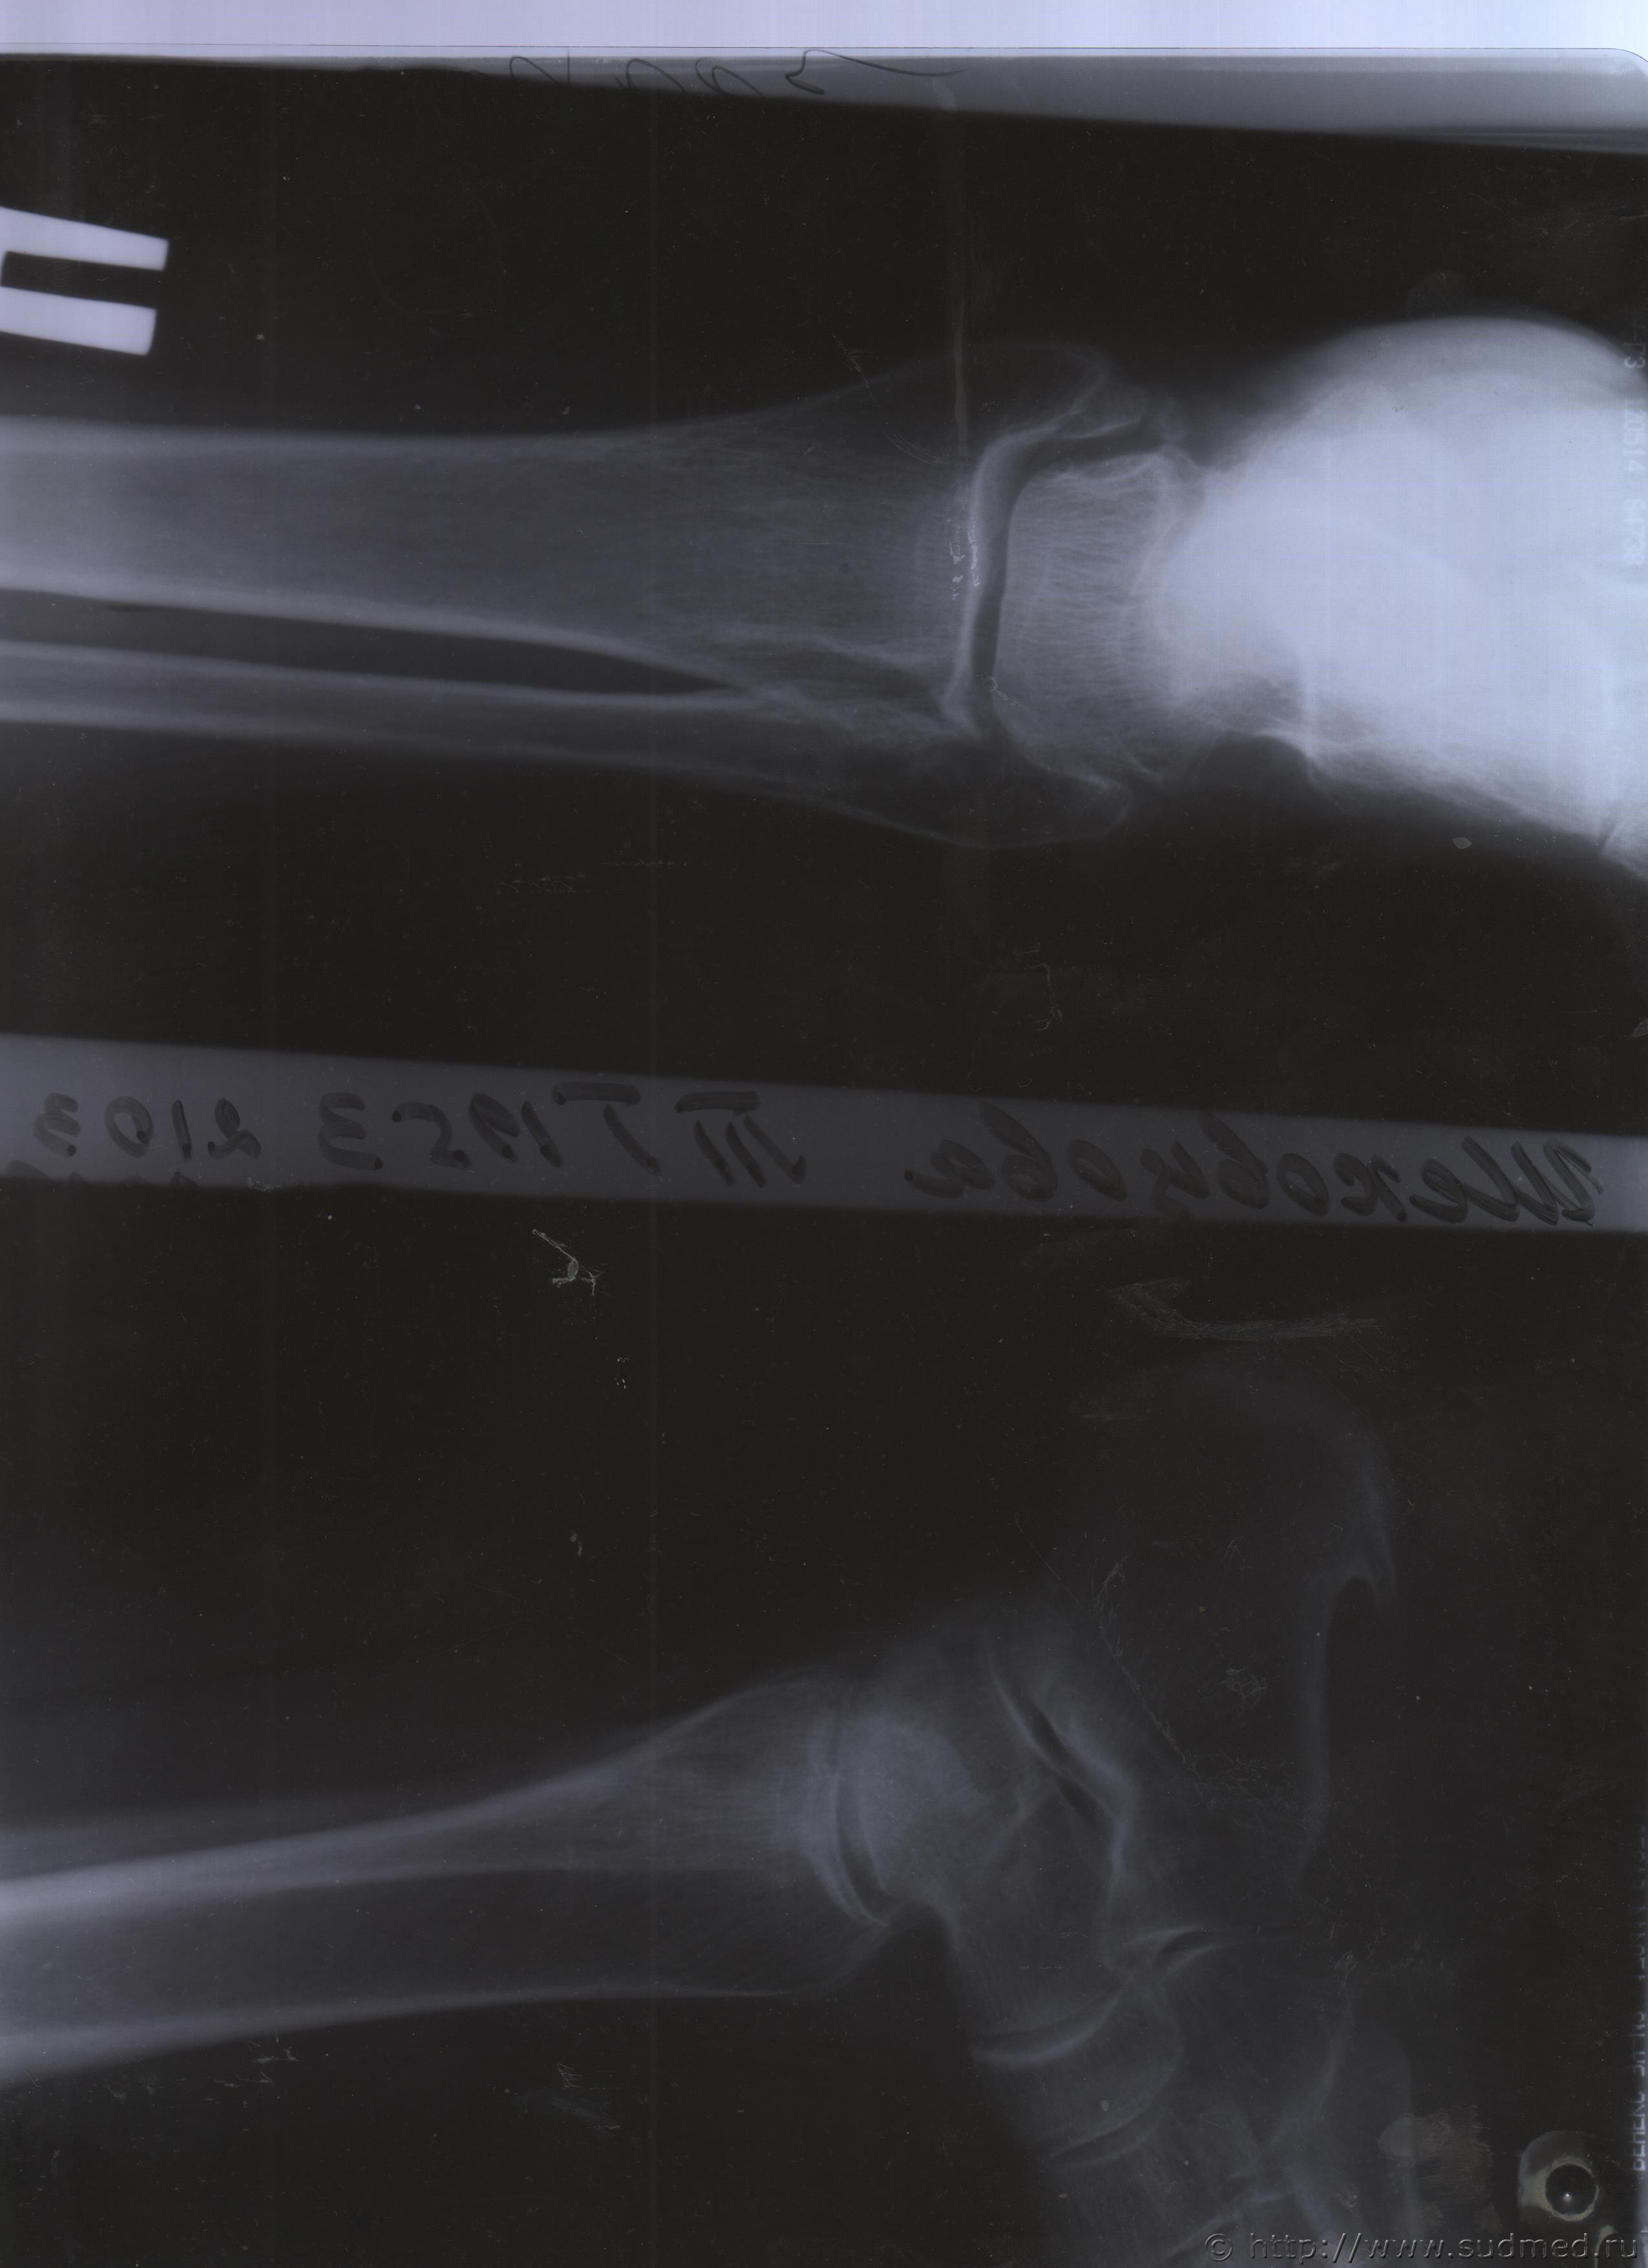

Уважаемые доктора, нужны ли снимки по перелому правой голени? и Заключения по МРТ и КТ.Ранее представляла результаты обследования...Сделала копию снимков по КТ и МРТ( только вот какого качества получились не знаю.)

Посмотрите, пожалуйста

с уважением Татьяна

Посмотрите, это снимки за 12 месяцев.

Эскизы прикрепленных изображений

Уважаемая Татьяна! По представленным Вами снимкам ничего сказать нельзя: нет маркировки даты каждого снимка (поэтому, невозможно их сравнивать друг с другом и соотносить с датой травмы), исследование непосредственно пленок гораздо более информативно, чем анализ представленных изображений (детали костной структуры в зоне перелома практически не видны).

Рекомендую проконсультировать все эти снимки у высококвалифицированного рентгенолога. Далее - по ситуации, т.е. в зависимости от его мнения. В любом случае, есть формальные основания для назначения дополнительной экспертизы, т.к., судя по представленному Вами фрагменту заключения эксперта, на экспертизу не были предоставлены все мед.документы с данными о лечении предъявляемой травмы (Вы пишете, что рентгенограммы делались на протяжении 12 месяцев, полагаю, что Вы и врачами наблюдались в течение этого срока, т.е. велась мед.карта).